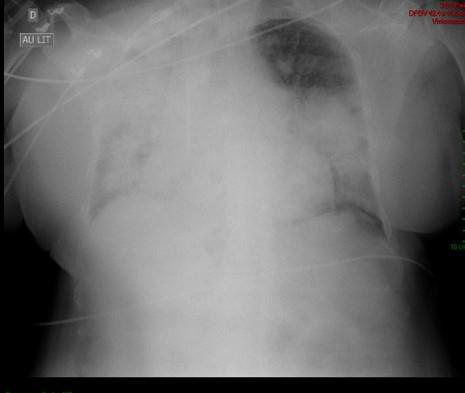

Étienne Crickx, La Revue du Praticien Radiographie thoracique F. Opacités alvéolaire périhilaires bilatérales prédominant à droite (hémorragie intra-alvéolaire).